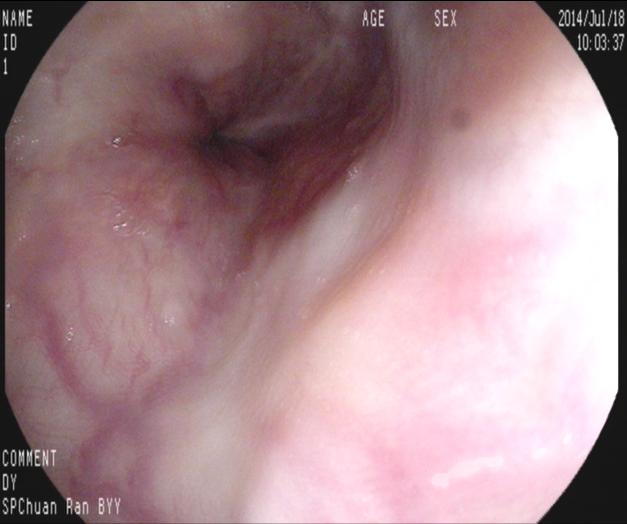

【九個(gè)月后復(fù)查】

九個(gè)月來(lái)患者無(wú)黑便及嘔血,復(fù)查胃鏡,食管內(nèi)曲張靜脈基本消失,胃底曲張靜脈亦減輕?;颊咴俅纬鲅L(fēng)險(xiǎn)而減低。如下圖:

上4圖隱構(gòu)可見(jiàn)套扎后癍痕,及右上方時(shí)鐘1點(diǎn)鐘位置略充盈的靜脈,無(wú)紅色征,不連續(xù)。